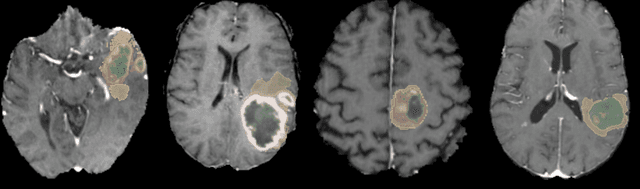

Brain tumor segmentation is a critical task for patient's disease management. To this end, we trained multiple U-net like neural networks, mainly with deep supervision and stochastic weight averaging, on the Multimodal Brain Tumor Segmentation Challenge (BraTS) 2020 training dataset, in a cross-validated fashion. Final brain tumor segmentations were produced by first averaging independently two sets of models, and then custom merging the labelmaps to account for individual performance of each set. Our performance on the online validation dataset with test time augmentation were as follows: Dice of 0.81, 0.91 and 0.85; Hausdorff (95%) of 20.6, 4,3, 5.7 mm for the enhancing tumor, whole tumor and tumor core, respectively. Similarly, our ensemble achieved a Dice of 0.79, 0.89 and 0.84, as well as Hausdorff (95%) of 20.4, 6.7 and 19.5mm on the final test dataset. More complicated training schemes and neural network architectures were investigated, without significant performance gain, at the cost of greatly increased training time. While relatively straightforward, our approach yielded good and balanced performance for each tumor subregions. Our solution is open sourced at https://github.com/lescientifik/xxxxx.